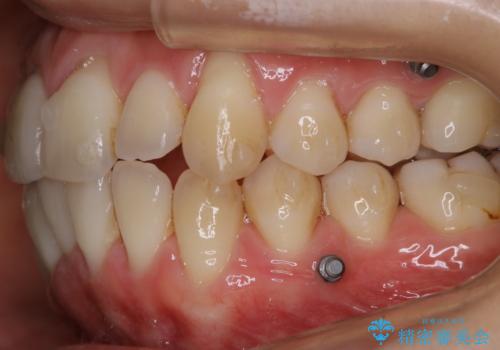

- インビザラインでの矯正治療中ですが、結婚式があるため全体の着色・ステインを綺麗にしたいとのことでした。PMTC60分コースを行いました。

PMTC(保険外治療)は、毎日の歯磨きで落としきれない汚れや、コーヒ、紅茶・タバコのヤニなどの着色も除去します。目には見えない歯と歯の間・歯肉の境目・インビザライン中はアタッチメント周囲などに残っているプラーク(歯垢)もしっかり取り除きます。PMTCでは専門的な機械や材料を使用して、徹底的に汚れを除去するため、虫歯・歯周病・口臭予防などにつながります。